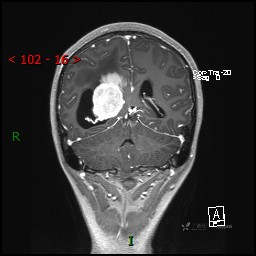

视物模糊发现颅内占位,“豆蔻年华”却承受开颅之痛,所幸一切顺利---结果公布~

患者年龄:14岁

简要病史:患者于1月前无明显诱因出现视物模糊,无明显头痛头晕,无恶心呕吐,无昏迷,无肢体偏瘫等症状,就诊于当地医院头部CT考虑:右侧丘脑、脑室占位。予以对症处置后家属为求进一步诊治来我科,以“颅内占位”收入院。 起病以来,精神、饮食、睡眠欠佳,大小便正常,体力下降,体重无明显变化。

临床诊断:脑室占位

CE